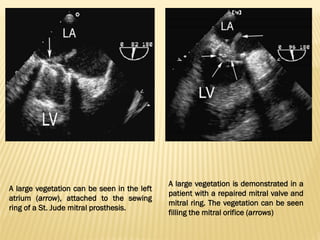

A large vegetation can be seen in the left

atrium (arrow), attached to the sewing

ring of a St. Jude mitral prosthesis.

A large vegetation is demonstrated in a

patient with a repaired mitral valve and

mitral ring. The vegetation can be seen

filling the mitral orifice (arrows)